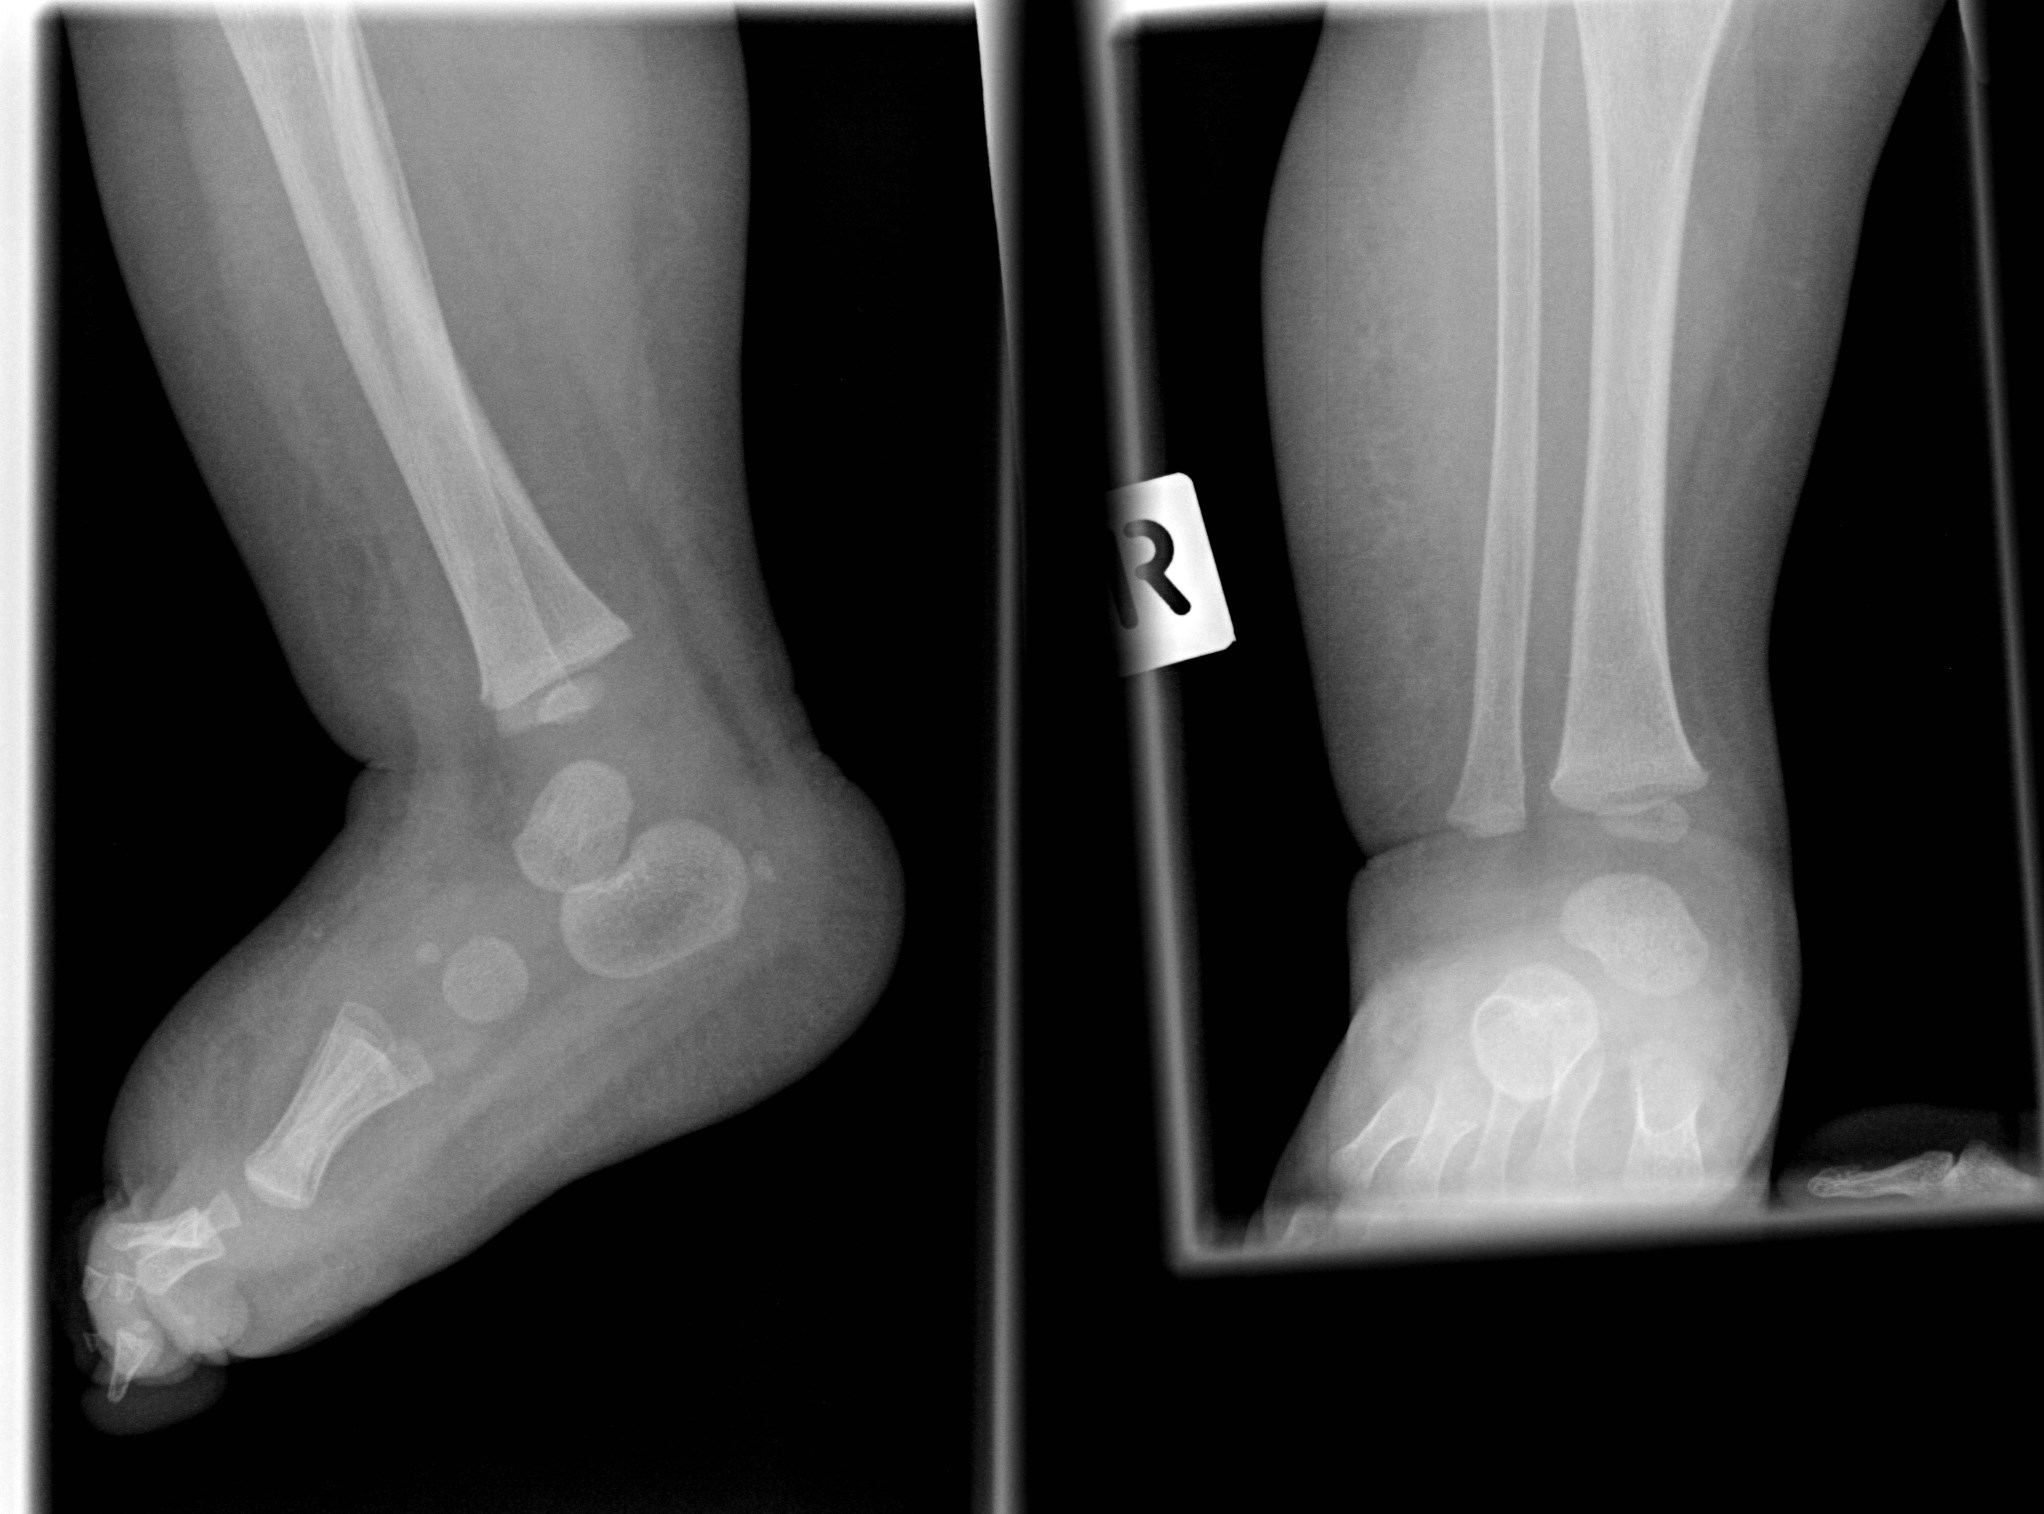

From www.researchgate.net

Lateral xray of left (A) and right (B) tibia and fibula. Download Pediatric Leg X Ray Leg and foot problems in childhood are common causes of parental concern. Pediatric tibial shaft fractures are the third most common long bone fracture in children. This view demonstrates the pediatric femur in its natural anatomical position allowing for assessment of suspected dislocations, fractures,. Intoeing is most common in infants and young children. Learn what your child might experience, how. Pediatric Leg X Ray.